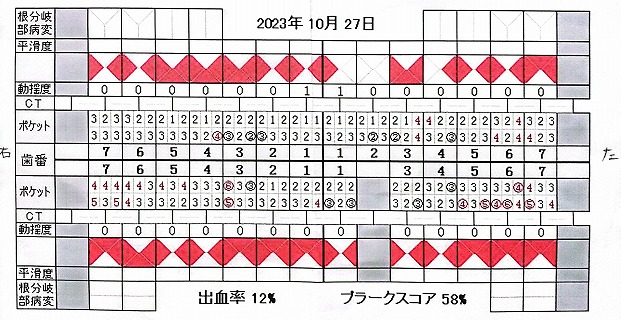

23.10.27 検査 PDF

23.10.27 検査 PDF